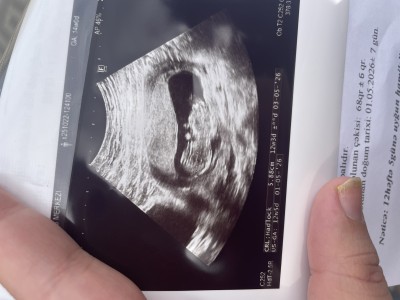

Cinsiyyet tahmini yapa bilirmisiniz kizlar

Gebelik haftası 12+4 haftasindayim cinsiyyet bilmek istiyorum

Erkek Diyorum tamamen kendi hissiyatım. Bide kesen fasulye gibi

Erkek gıbı canm